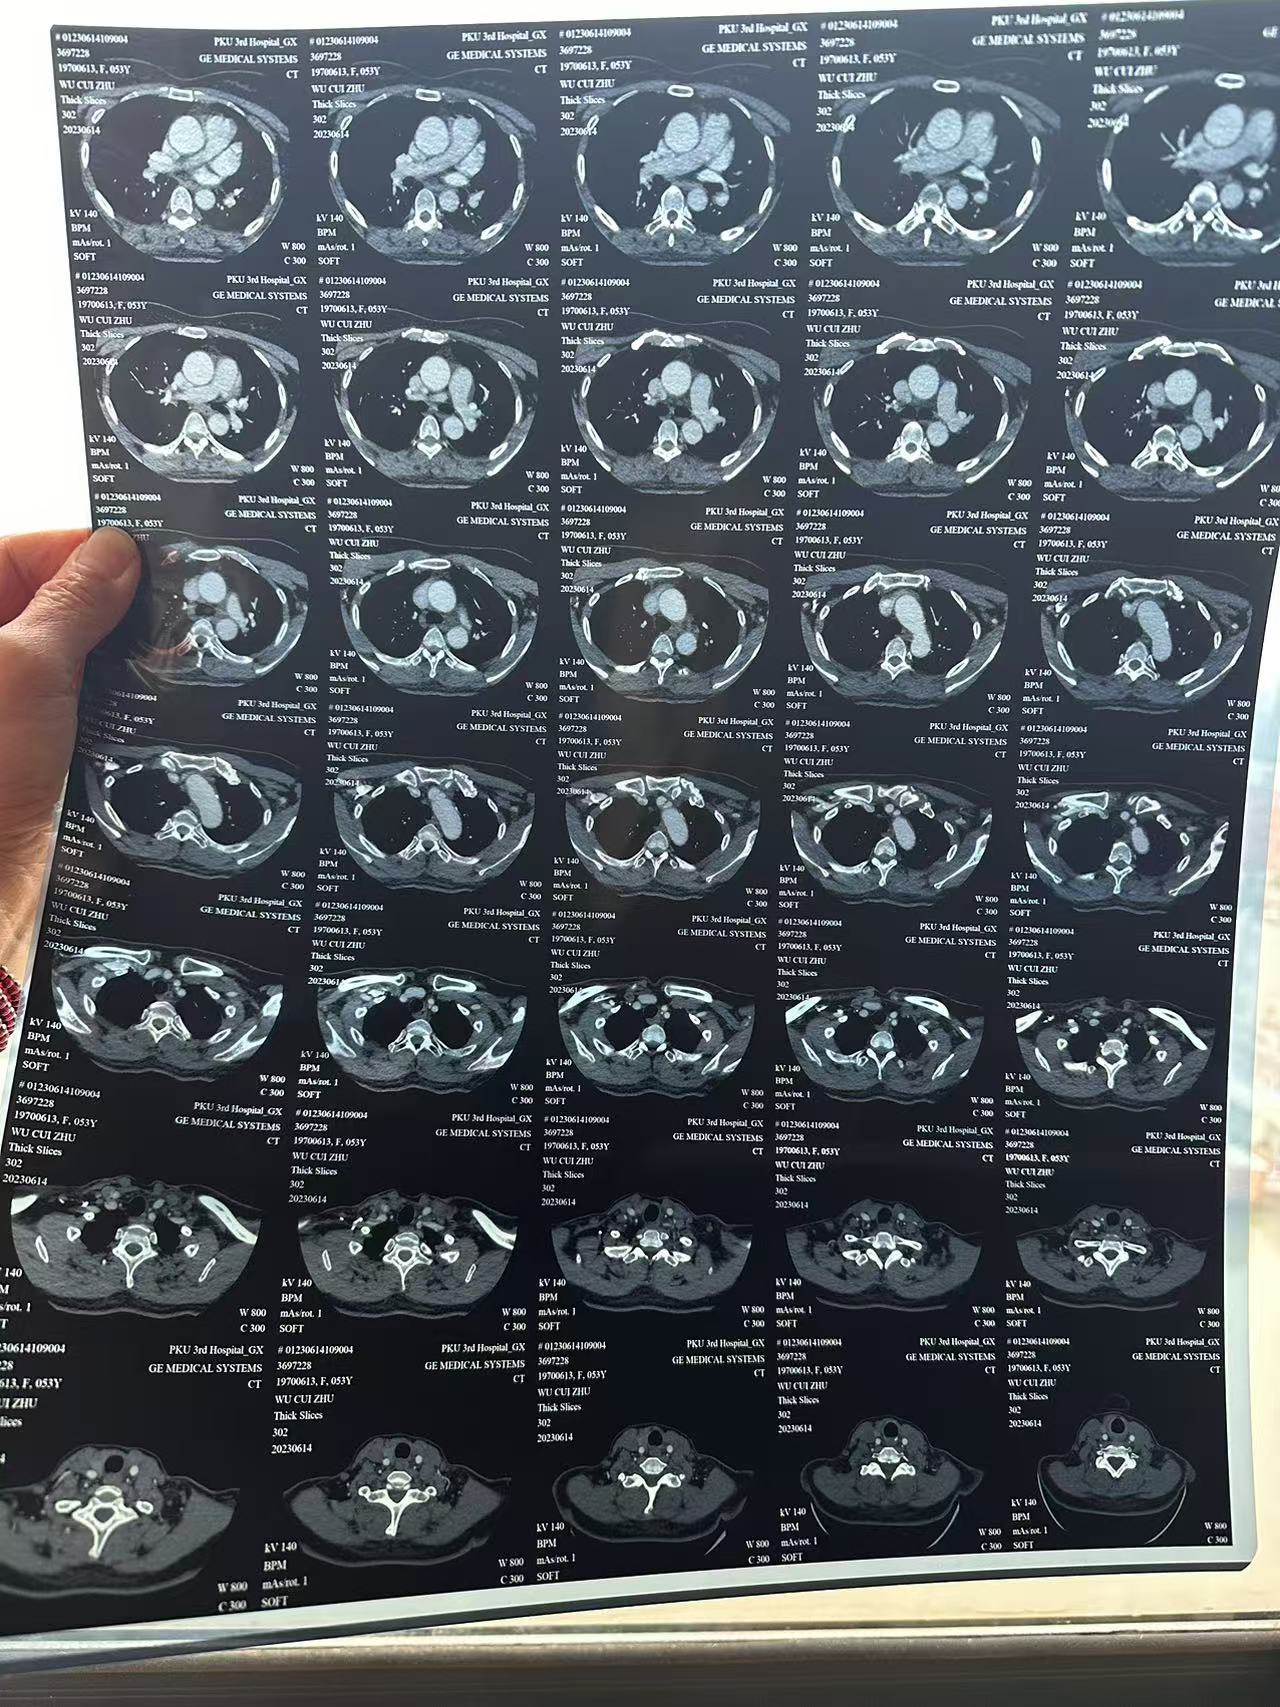

• 诊断:寰枢椎脱位,颅底凹陷

• 日期:2023.09

• 医院:北三医院

• 主刀:王超

• 术后影像: